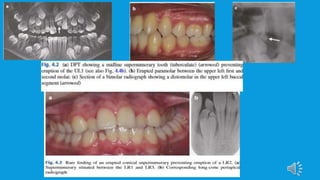

 Routine radiographs such as dental panoramic radiographic, upper standard

occlusal and long-cone periapical can be used in combination to localize a

supernumerary tooth using the parallax technique (horizontal or vertical tube

shift) and may give sufficient information to allow safe removal.

However, if the proximity to developing roots is a concern, assessment of

resorption is required or a decision to whether orthodontic tooth movement

can go ahead without removal of supernumerary tooth, then CBCT may be

indicated.This additional imaging technique has shown to enhance the ability

to localize a supernumerary.

• 23.

• 24.

Can you identifythe location?

• 25.

Can you identifythe morphology?